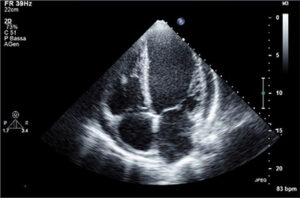

ECOCARDIOGRAMMA

Ecocolordoppler cardiaco